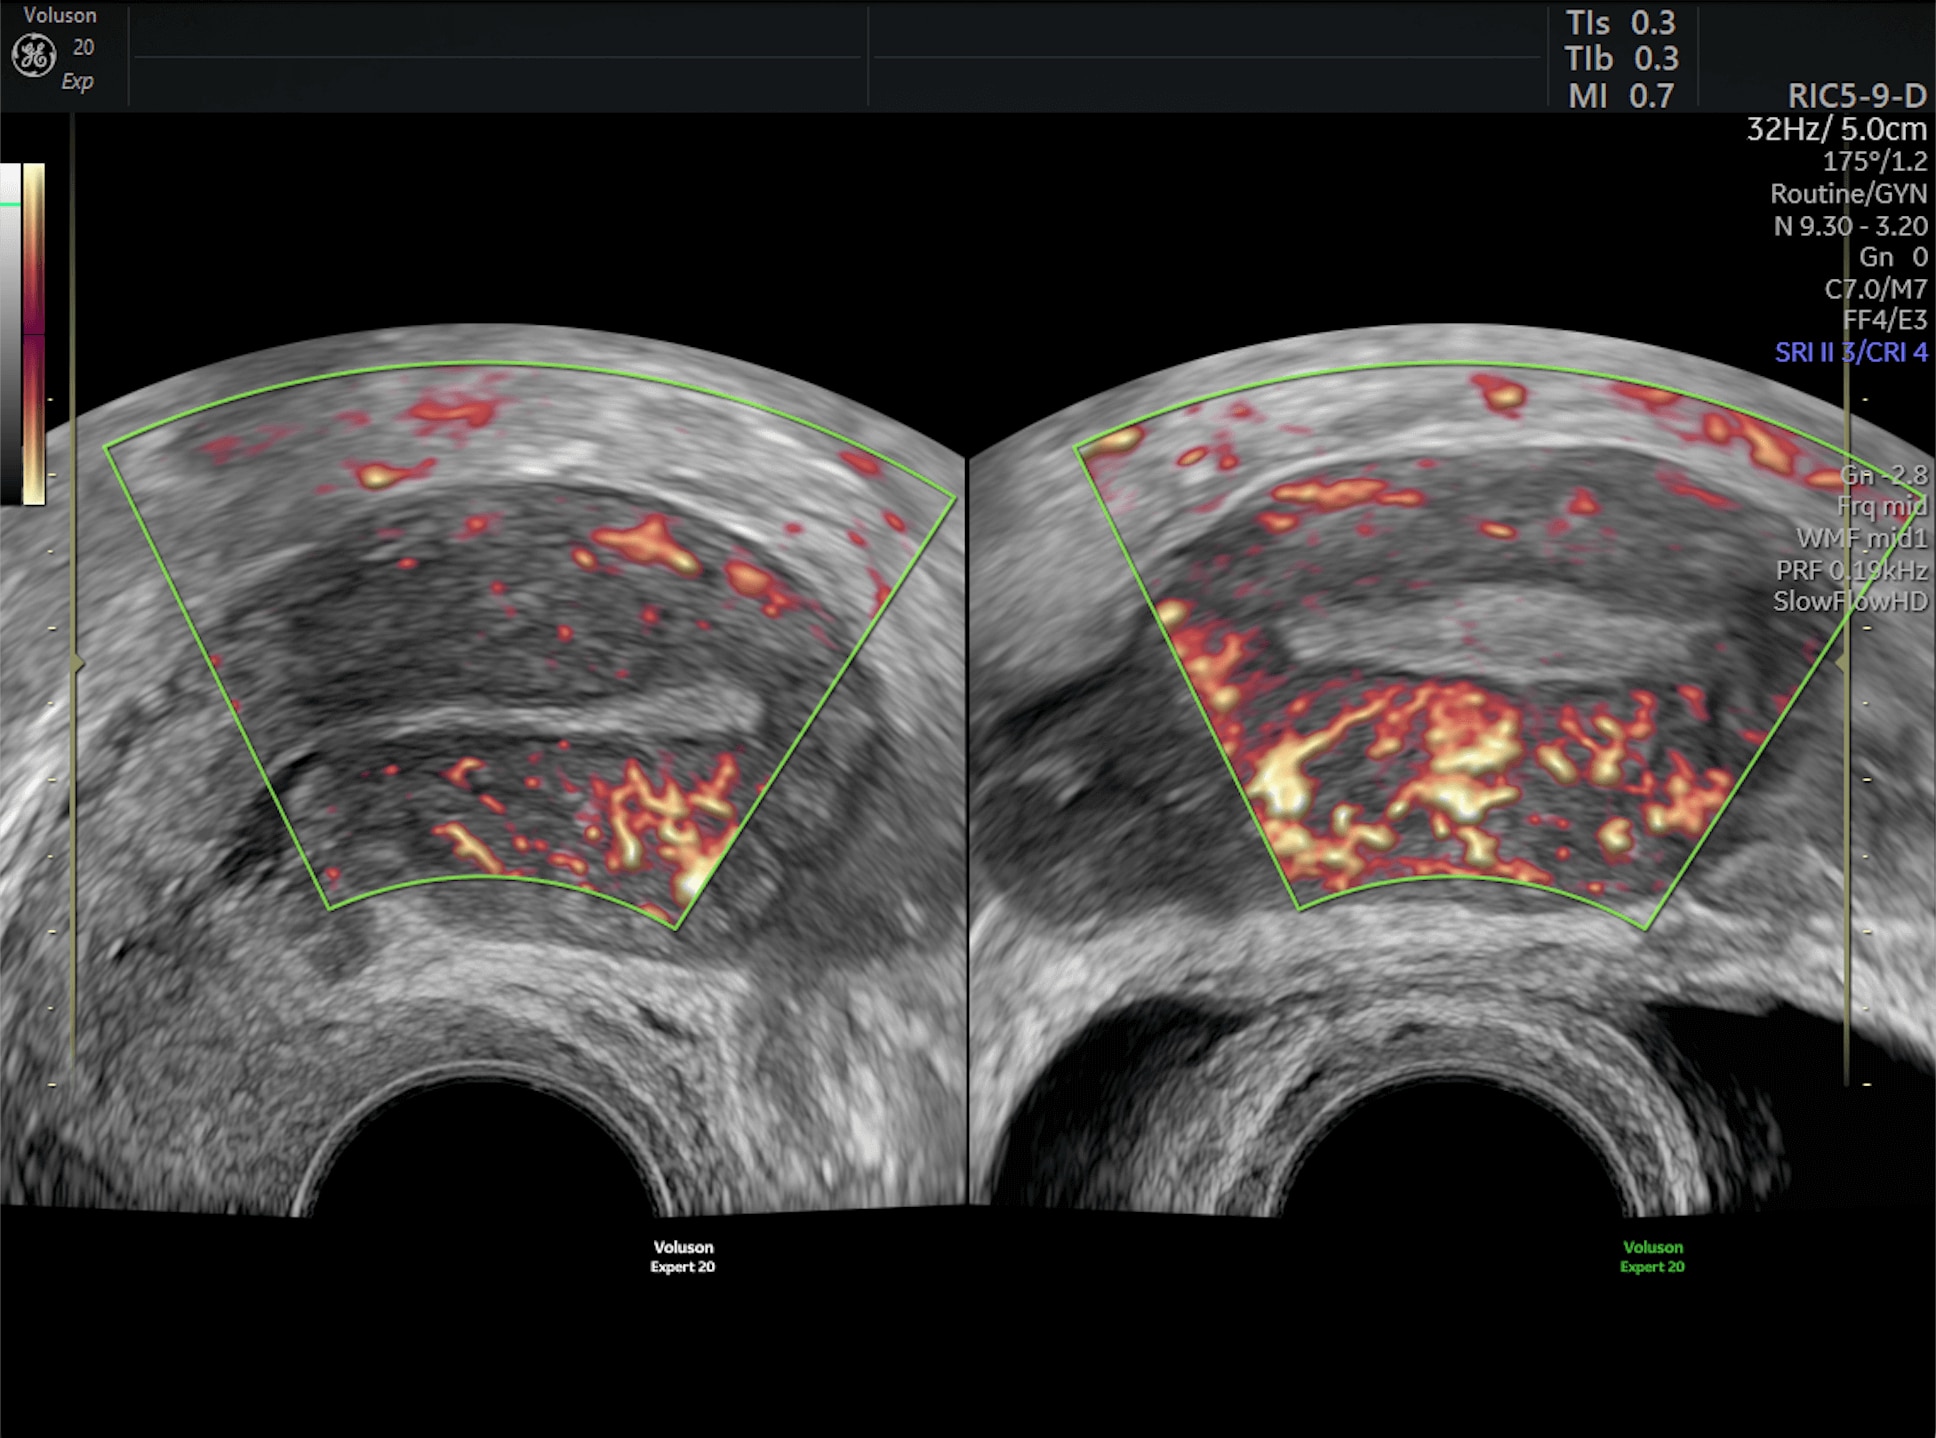

Amplify imaging performance and simplify scanning with our most advanced architecture

Refine Clinical Insights

Extraordinary clarity and definition so you can focus on early detection and intervention.

Faster.Sharper. Clearer.

Faster.Sharper. Clearer.